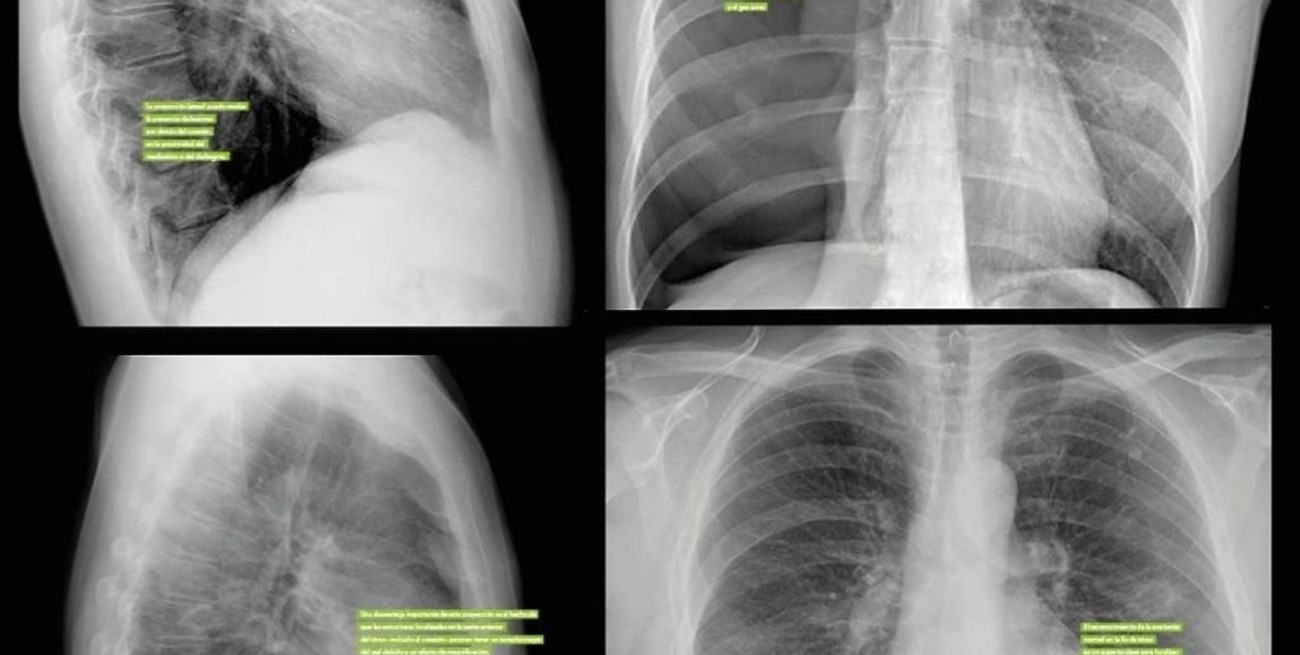

Un egresado de la Universidad Nacional de Córdoba (UNC) diseñó un programa informático que, mediante inteligencia artificial, permite llevar a texto informes de estudios médicos, como radiografías y ecografías, lo que facilita el trabajo de los profesionales de la medicina.

Garay explicó que, para crear la herramienta, utilizó una arquitectura provista para la descripción de imágenes genéricas y la aplicó al dominio médico para que genere automáticamente el informe médico.

Garay utilizó una base de datos abierta compuesta de 3.851 radiografías de la Universidad de Indiana en Estados Unidos para "entrenar" a la red neuronal.